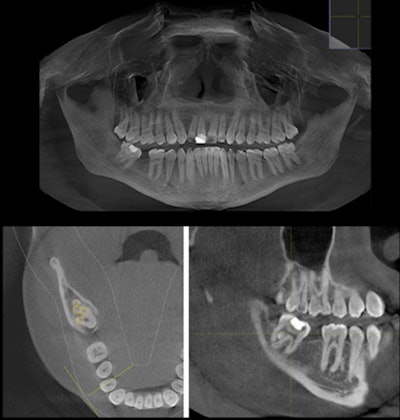

Therefore, the man underwent a CBCT scan, which showed the pulp chamber was continuous, and the tooth had five canals. It had two orifices on the mesial, two in the middle, and one on the distal side.